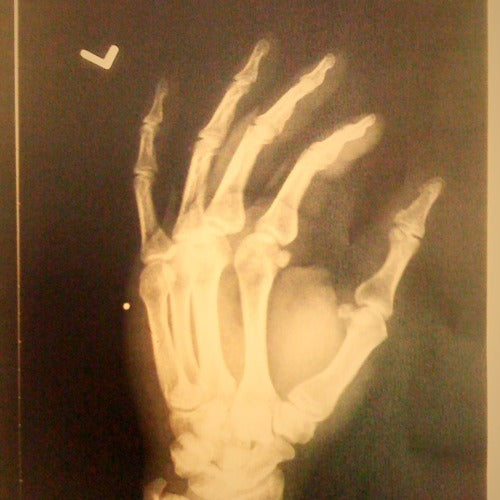

I broke my hand having the best day on the bike in a long time. Hope to get back to Santa Cruz with Garrett when this cast comes off!